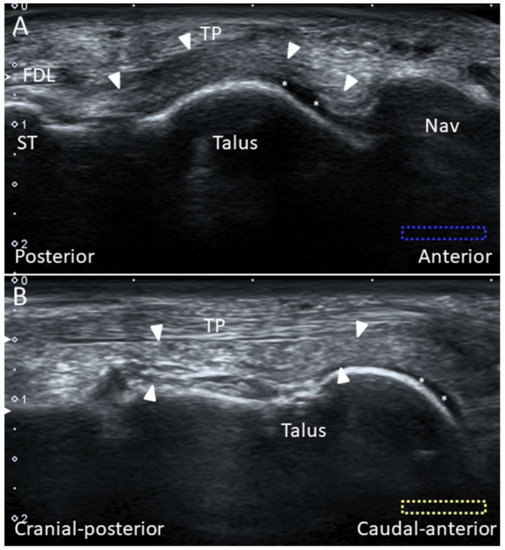

4.3. Tibialis Posterior Tendon

4.3.1. Anatomy

4.3.2. Scanning Technique

4.3.3. Clinical Relevance